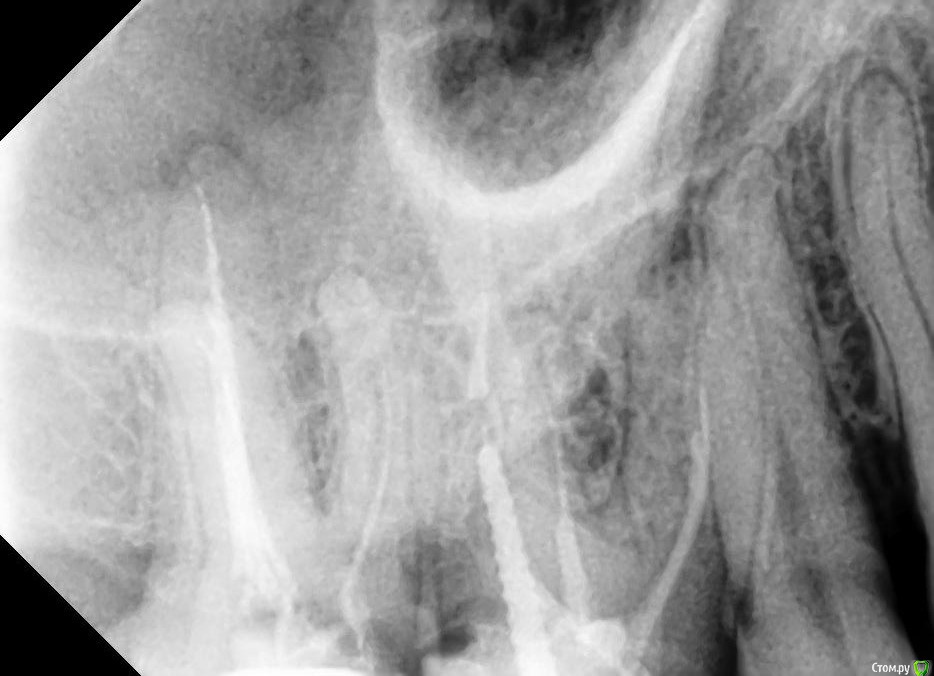

khelsa Опубликовано 28 апреля, 2020 Поделиться Опубликовано 28 апреля, 2020 Что скажете по поводу этого зуба , пациент лечил месяц назад , болезненность при накусывании Ссылка на комментарий

vse32 Опубликовано 28 апреля, 2020 Поделиться Опубликовано 28 апреля, 2020 В МБ, похоже, инструмент сломан. Дистально как будто зуб сильно разрушен. Надо очно смотреть. А так, прогноз малоприятный.1.7 тоже с гранулемой. Ссылка на комментарий